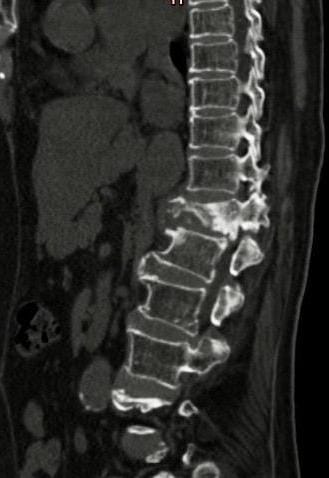

केस के सम्बन्ध में विस्तृत जानकारी देते हुए डॉ. विवेक पात्रे बताते हैं कि वेसलप्लास्टी की सुविधा इससे पहले केवल महानगरों के बड़े अस्पतालों में ही होती थी लेकिन यह पहली बार है जब राज्य के किसी अस्पताल में इस प्रकार की नई तकनीक से वेसलप्लास्टी की गई है। महिला को डी (डॉर्सल)12 वर्टेब्रल फ्रेैक्चर था जिसके कारण पिछले 9 महीने से असहनीय दर्द के कारण परेशान थी और एक महीने से वह बैठ नहीं पाती थी। सुई की छेद से की गई पूरी प्रक्रिया के बाद महिला आधे घंटे के बाद बैठने में समर्थ हो गई और उसे उसी दिन डिस्चार्ज कर दिया गया। हालांकि इतने अधिक उम्र के मरीजों में कोई भी प्रक्रिया काफी जोखिम भरा रहता है फिर भी रिस्क लेते हुए हमारी टीम ने इस प्रक्रिया के लिए तैयारी की। हमारे पास इस प्रक्रिया के लिए बीच के तीन मिनट बेहद अहम होते हैं जब पॉलीमेथिल मेथाक्रिलेट यानी बोन सीमेंट को तैयार कर तीन मिनट के भीतर ही इंजेक्ट करना रहता है क्योंकि यदि इसमें देरी की गई तो बोन सीमेंट बाहर के वातावरण में तुरंत ठोस अवस्था में परिवर्तित हो जाता है और जिस स्थान पर है वहीं जम जाता है इसीलिए बोन सीमेंट को प्रोसीजर से पहले फ्रिज के अंदर बेहद कम तापमान में रखा गया जिससे कि बॉडी में इंजेक्ट करने के दौरान वह देरी से जमे।

डॉ. विवेक पात्रे बताते हैं कि वेसलप्लास्टी एक इमेजिंग-निर्देशित (इमेज गाइडेड) प्रक्रिया है जो वर्टेब्रल कम्प्रेशन फ्रैक्चर के उपचार के लिए एक सुरक्षित विधि प्रदान करता है। इसके लिए सबसे पहले जिस जगह पर वेसलप्लास्टी किया जाता है उस जगह को सुन्न किया गया। उसके बाद वहां मोटी सुई डाली। उस मोटी सुई के अंदर से मेनुअल ड्रिल के जरिये वर्टेब्रल बॉडी में निश्चित स्थान पर जगह बनाई। फिर उस जगह पर फ्लूरोस्कोपी एवं डीएसए मशीन में देखते हुए बोन सीमेंट (अस्थि सीमेंट) को नीडिल की सहायता से बैलून कंटेनर के अंदर इंजेक्ट किया गया। बैलून छिद्रयुक्त होता है जिसके कारण अस्थि सीमेंट की एक छोटी सी मात्रा इसकी दीवार से होकर गुजरती है और वर्टेब्रल बॉडी के अंदर छिद्रों के माध्यम से स्थापित हो जाती है। बैलून के छिद्रयुक्त संरचना के कारण ही वर्टेब्रल बॉडी से सीमेंट का रिसाव एवं फैलाव नहीं होता है जिसके कारण यह स्पाइनल कैनाल या फेफड़े में नहीं फैलता और जटिलता की संभावना नहीं रहती है ।